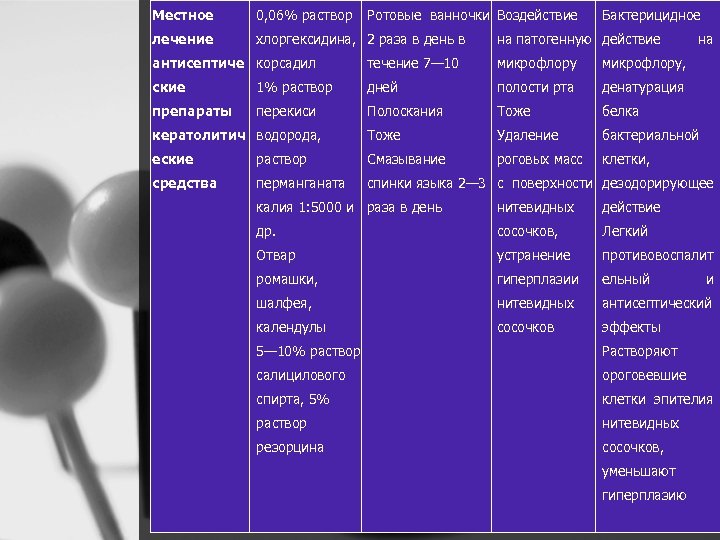

Местное 0, 06% раствор Ротовые ванночки Воздействие Бактерицидное лечение хлоргексидина, 2 раза в день в на патогенную действие на антисептиче корсадил течение 7— 10 микрофлору, ские 1% раствор дней полости рта денатурация препараты перекиси Полоскания Тоже белка кератолитич водорода, Тоже Удаление бактериальной еские раствор Смазывание роговых масс клетки, средства перманганата спинки языка 2— 3 с поверхности дезодорирующее калия 1: 5000 и раза в день нитевидных действие др. сосочков, Легкий Отвар устранение противовоспалит ромашки, гиперплазии ельный шалфея, нитевидных антисептический календулы сосочков и эффекты 5— 10% раствор Растворяют салицилового ороговевшие спирта, 5% клетки эпителия раствор нитевидных резорцина сосочков, уменьшают гиперплазию